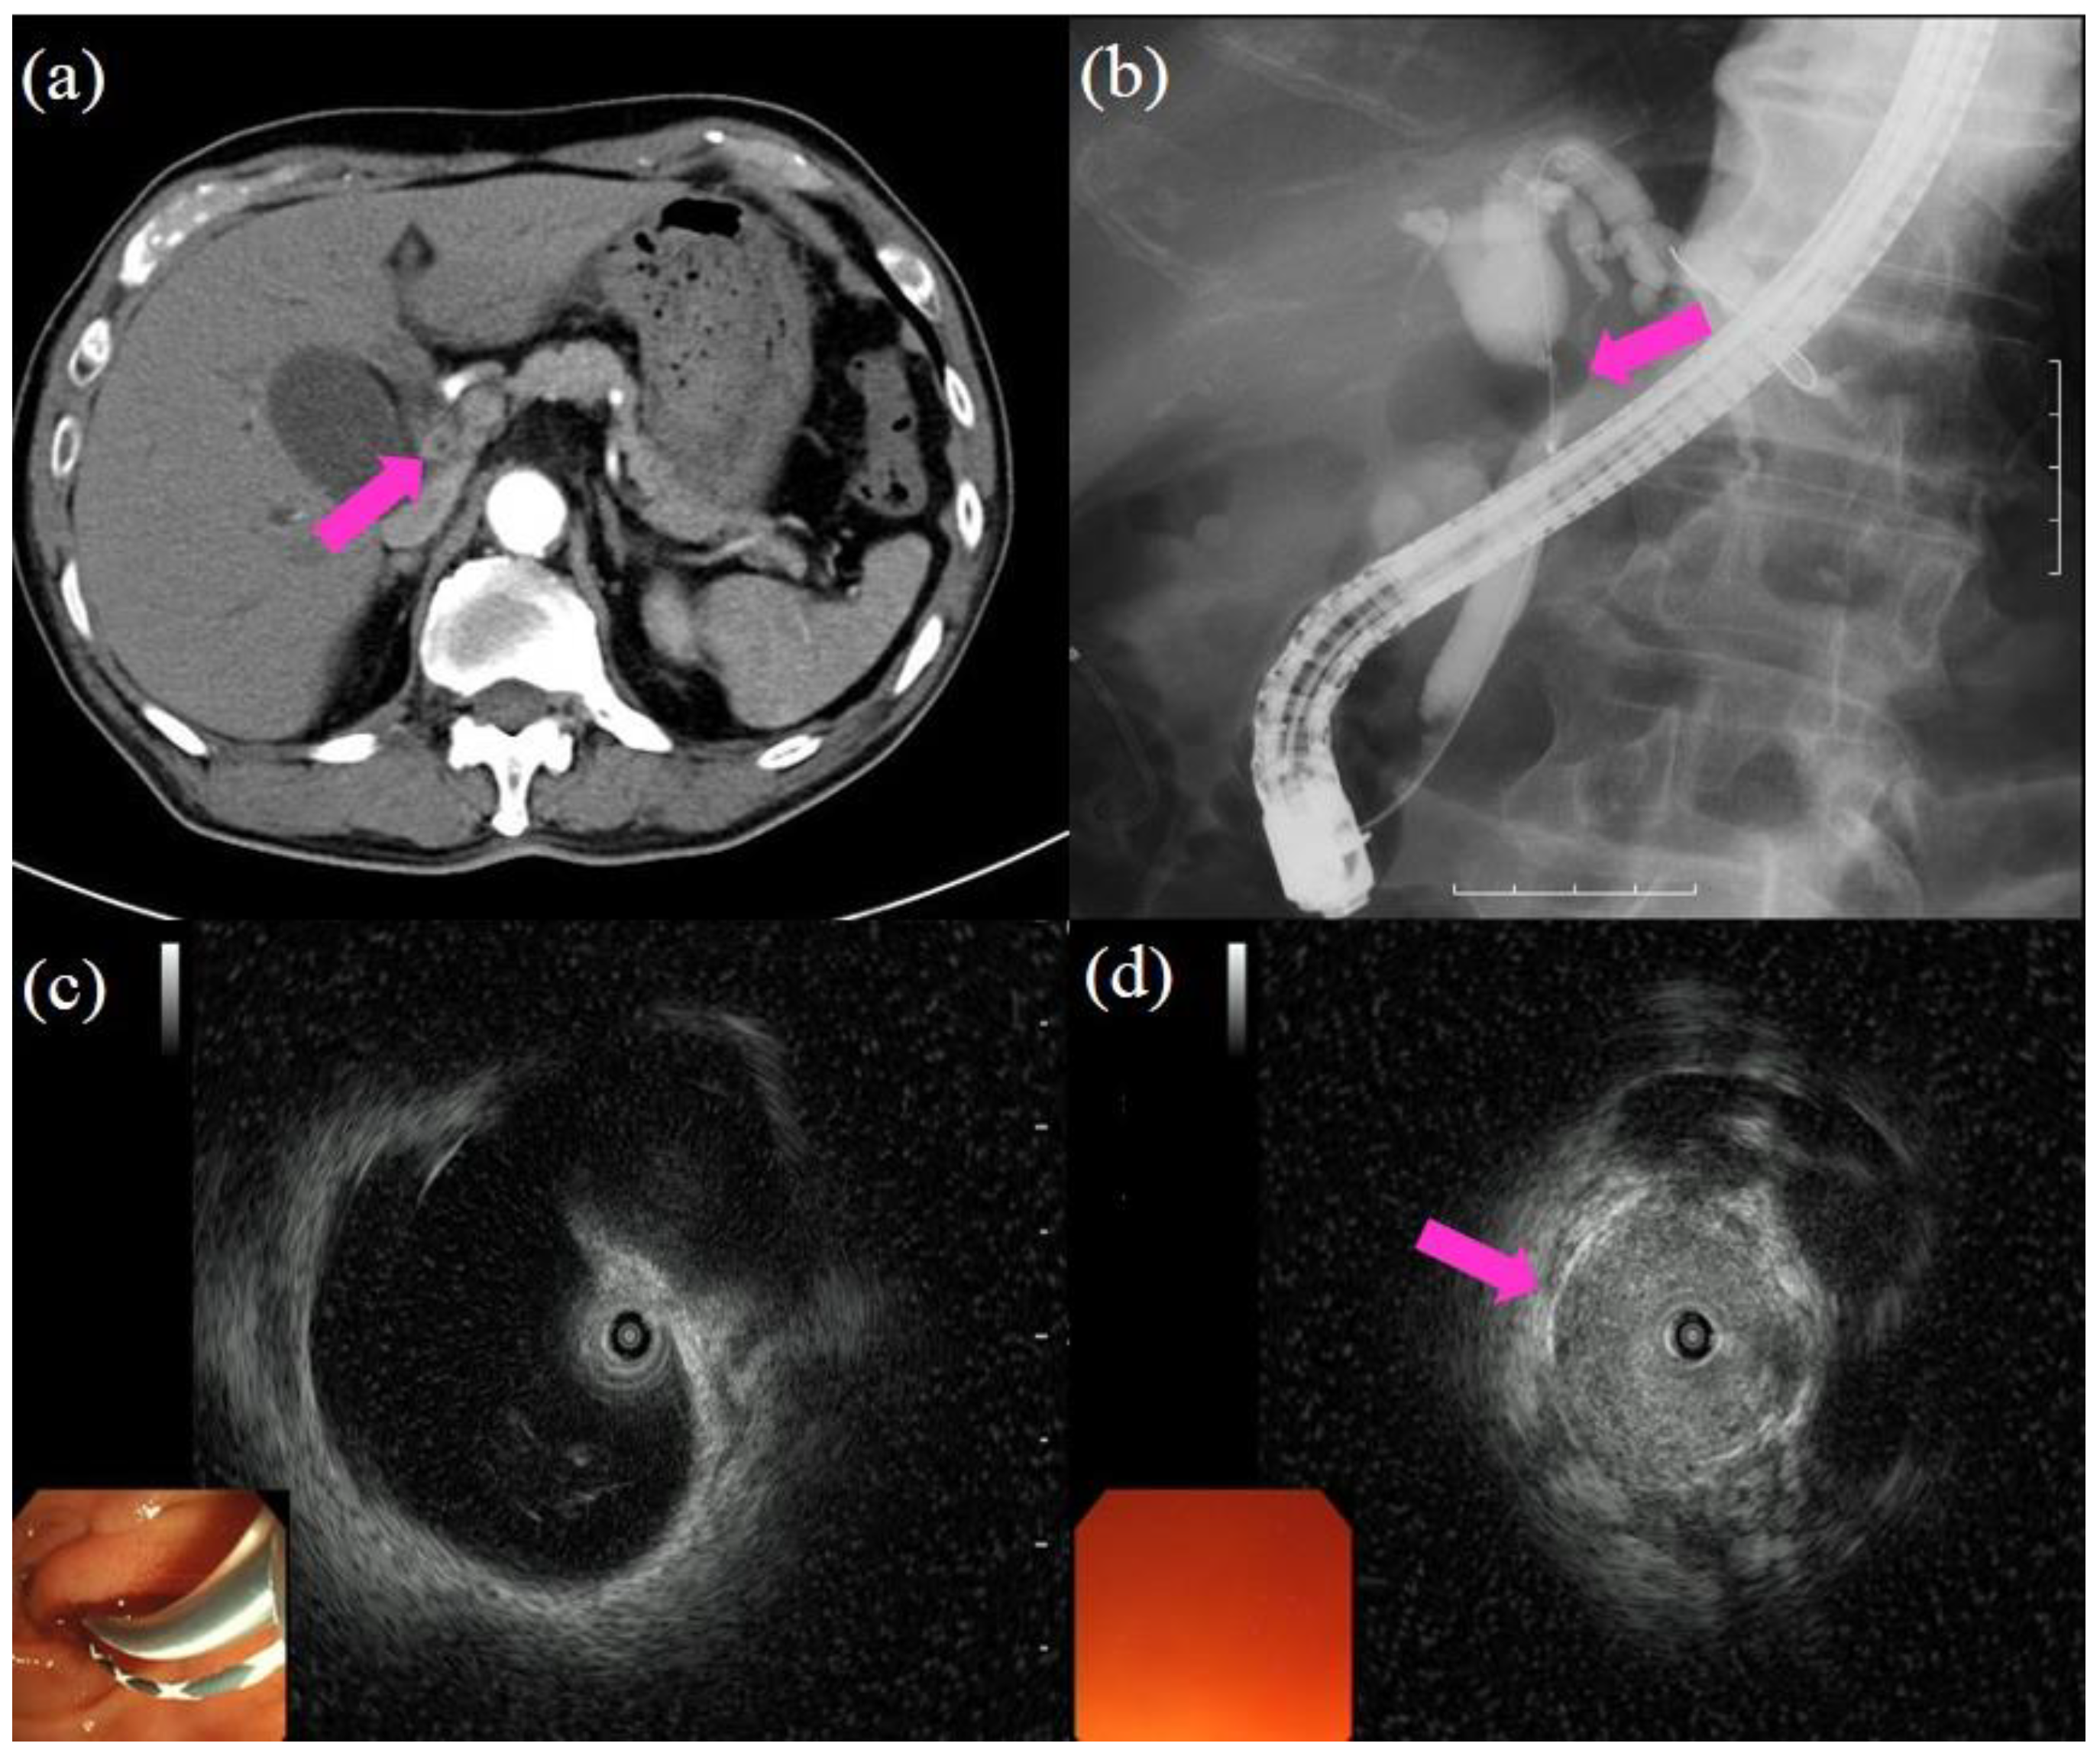

Since its introduction in 1968, endoscopic retrograde cholangiopancreatography (ERCP) has been an essential and established procedure for the diagnosis and treatment of biliopancreatic diseases. The success rate of the procedure has been reported to be approximately 95% [20,21], and it is still considered the gold standard for biliary imaging. A duodenoscope is advanced to the ampulla, and an ERCP catheter is inserted into the biliary tract over a guidewire. Following cannulation of the biliary tract, the contrast medium is injected for cholangiography. When performing ERCP, the interpretation of the cholangiography findings is the first step. An accurate distinction between benign and malignant biliary strictures is needed. Malignancy is suggested when the cholangiography shows strictures that are longer than 10 mm, asymmetric, and irregular. Benign disease is suggested when cholangiography shows short, regular, and symmetric strictures. Using these criteria, the diagnostic sensitivity and specificity for cholangiography findings were reported to be 74% and 70%, respectively [22]. After cholangiography, intraductal ultrasound (IDUS) is performed to detect the main lesion. Moreover, superficial extension from the main lesion or vascular invasion could be confirmed using IDUS [23,24,25]. A large retrospective study reported a sensitivity of 93.2%, a specificity of 89.5%, and an accuracy of 91.4% for the evaluation of malignant strictures [26]. When inserting the IDUS catheter into the bile duct, some cases are difficult due to the tension in the sphincter of Oddi. In such cases, endoscopic sphincterotomy may be performed. When inserting the IDUS catheter over the stricture, balloon dilation may be performed to pass the stricture. However, it should be limited for mandatory cases where investigation of proximal superficial extension is required because it might damage the main lesion. Figure 1 shows the procedures of cholangiography and IDUS.

Figure 1.

Procedures of cholangiography and intraductal ultrasound (IDUS): (a) computed tomography showing the wall thickness in the bile duct (pink arrow); (b) cholangiography showing the biliary stricture in the hilar bile duct (pink arrow); the proximal part of the bile duct shows dilatation; (c) IDUS showing dilatation in the proximal part of the bile duct and no lesion; (d) IDUS showing a lesion in the biliary stricture (pink arrow).